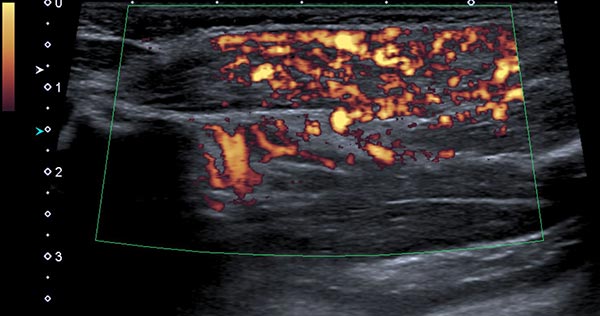

In der Power-Dopplersonographie zeigt sich eine starke Perfusion der Raumforderung, sodass von einem vaskulären Tumor ausgegangen wird. Die starke Blutströmung wird hier orange im B-Bild dargestellt, die Strömungsrichtung ist dabei nicht farbkodiert.

Die Power-Dopplersonographie Ende des 8. Lebensmonats zeigt nicht nur eine Volumenzunahme des subkutanen Tumors, sondern auch eine nochmals stark gesteigerte Perfusion (orange farbkodiert).